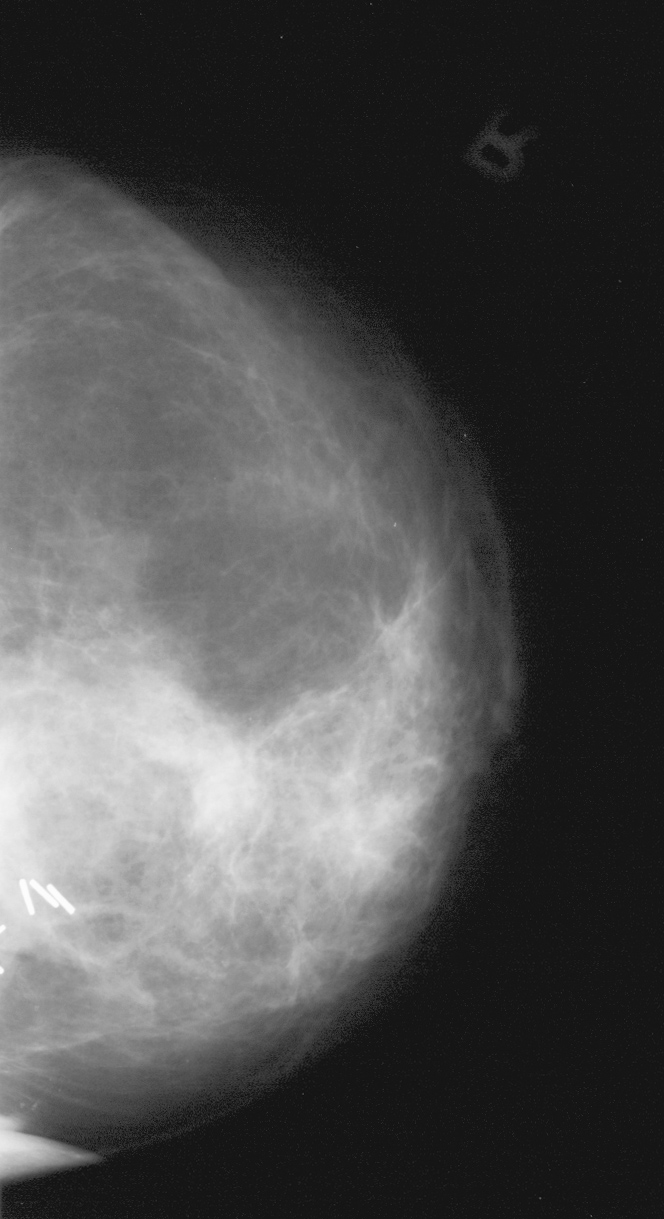

◂Breast Anatomy